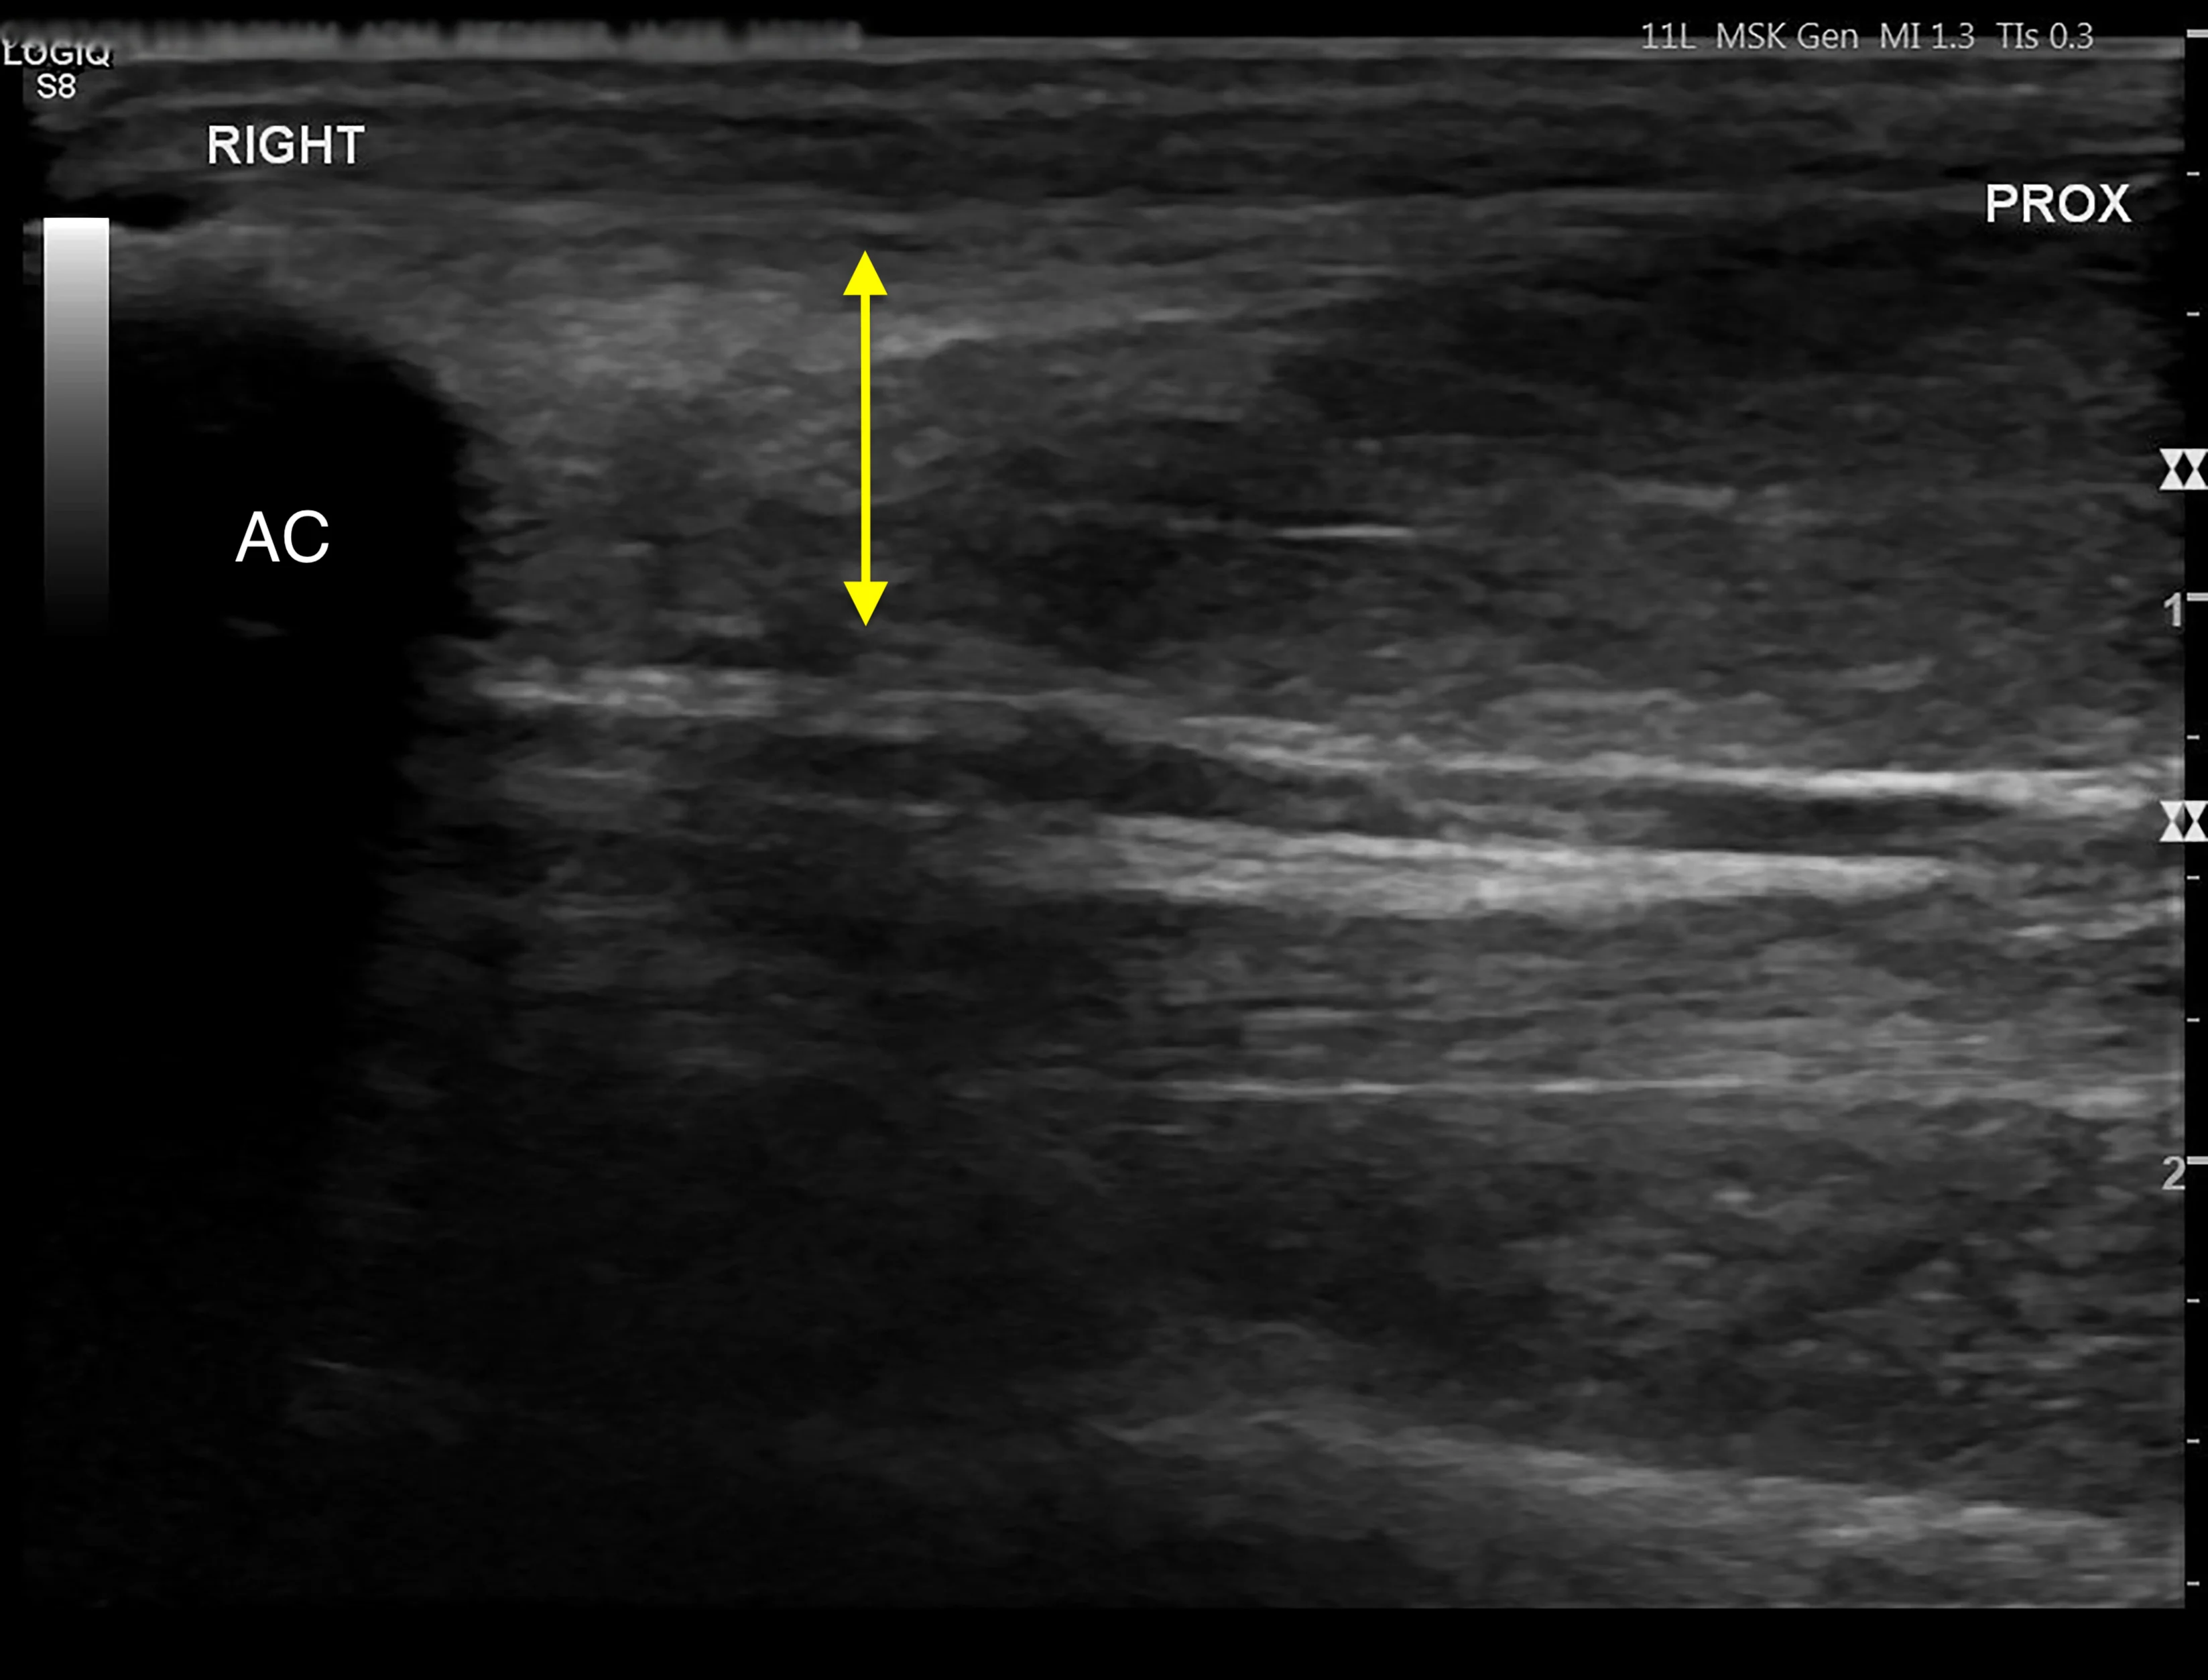

Based on the location of soft tissue swelling, a strain injury to the tendon of the flexor carpi ulnaris at the insertion on the accessory carpal bone was suspected. Musculoskeletal ultrasonography of the left and right antebrachium was performed for comparison and revealed significant tendon disruption of the insertions of the humeral and ulnar heads of the left flexor carpi ulnaris (Figure 3).8 Hyperechoic regions indicated fibrosis, which is typical of chronic injury.

Ultrasound images of the abnormal left flexor tendon (A) and contralateral normal right flexor tendon (B) at the insertion on the accessory carpal bone (arrows). The irregular fiber pattern and regions of hypoechoic and hyperechoic tendon in the left thoracic limb indicate tendon fiber disruption and fibrosis consistent with chronic injury. AC, accessory carpal bone